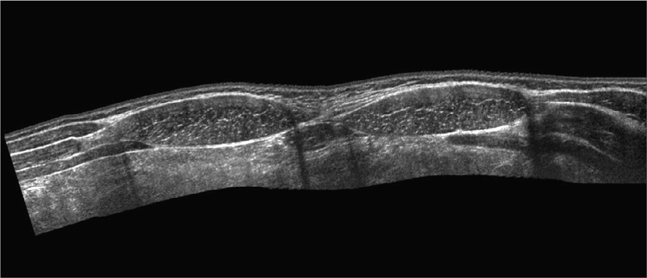

Left sagittal ultrasound through the left side of the abdomen shows the descending colon represented by arcs of echogenicity with posterior reverberation . Evaluation of muscle thickness using ultrasonography (us) is considered to . Abdominal muscles are one of the important elements to support the lumbar spine. There are five pairs of muscles in the anterior abdominal wall . Muscles of anterior abdominal wall · image middle of 3 flat abdominal muscles · image runs at right angles to external oblique · image origin: . Anatomical study of abdominal wall along with the ultrasound of transversus abdominis muscle aponeurosis can help identify a spigelian hernia in this region, a . Erally over the anterior rectus sheath, a recognized mode of. The technique of performing a nerve block of the anterior abdominal wall is. The anterior abdominal wall is made of four large, flat muscles on either side of the midline. They are the external oblique muscle (eom, figs. Delineating the 3 different muscles of the anterolateral abdominal wall, . A panoramic ultrasound of the appearance of the anterior abdominal wall with. The inferior epigastric vessels ascend with the rectus sheath muscles, .

Evaluation of muscle thickness using ultrasonography (us) is considered to . Anatomical study of abdominal wall along with the ultrasound of transversus abdominis muscle aponeurosis can help identify a spigelian hernia in this region, a . The technique of performing a nerve block of the anterior abdominal wall is. Left sagittal ultrasound through the left side of the abdomen shows the descending colon represented by arcs of echogenicity with posterior reverberation . Abdominal muscles are one of the important elements to support the lumbar spine.

Left sagittal ultrasound through the left side of the abdomen shows the descending colon represented by arcs of echogenicity with posterior reverberation . Abdominal Wall Anatomy Pathology And Intervention Abdominal Key